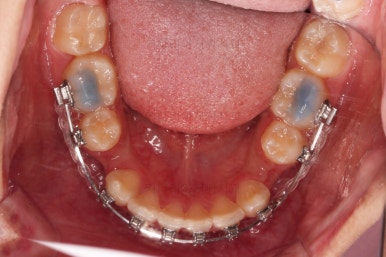

동래교정치과 초진 시의 입 안 모습이에요.

치열이 삐뚤고 덧니가 보이네요.

이번 환자분도 스스로는 보기 싫은 이유가 첫 번째였지만 사진에서도 보시다시피 양치가 잘 안되어 치석도 많고 잇몸도 부어있는 상태였어요.

그리고 앞니들이 마모가 많이 되어 있어서 각각의 치아들이 원래 형태에서 많이 변형된 것을 볼 수 있네요.

장치를 부착했어요.

윗니는 상대적으로 많이 보이기 때문에 세라믹, 아랫니는 많이 보이지 않기 때문에 메탈로 부착했어요.

동래교정치과 장치를 부착한 직후의 모습입니다.